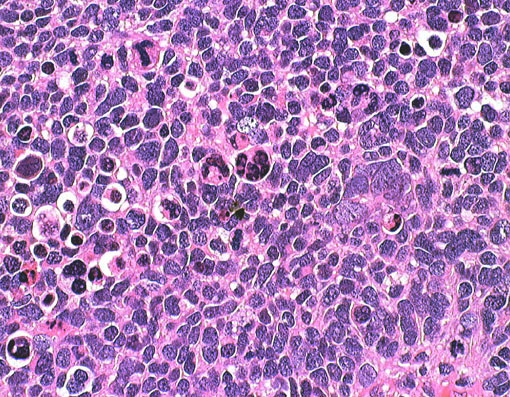

左は1歳児に発生した一部に神経芽細胞腫様の分化 row of the tumor cells (or neuronal differentiation) を伴う髄芽腫 medulloblastoma with extensive nodularity(小脳神経芽細胞腫 cerebellar neuroblastomaともいわれたもの)。右は7歳児の退形成(核の異形成)が顕著な退形成性髄芽腫 anaplastic medulloblastomaです。前者の治癒率は高く,後者の病理像の治癒率は極めて低いものです。